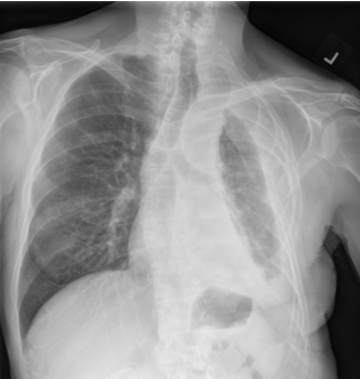

Chest X-ray showing a large fluid buildup around the left lung, which can be caused by mesothelioma and may lead to breathing difficulty.

Chest X-ray showing a large pleural effusion (fluid buildup) around the left lung, which can be caused by mesothelioma and may lead to breathing difficulty.